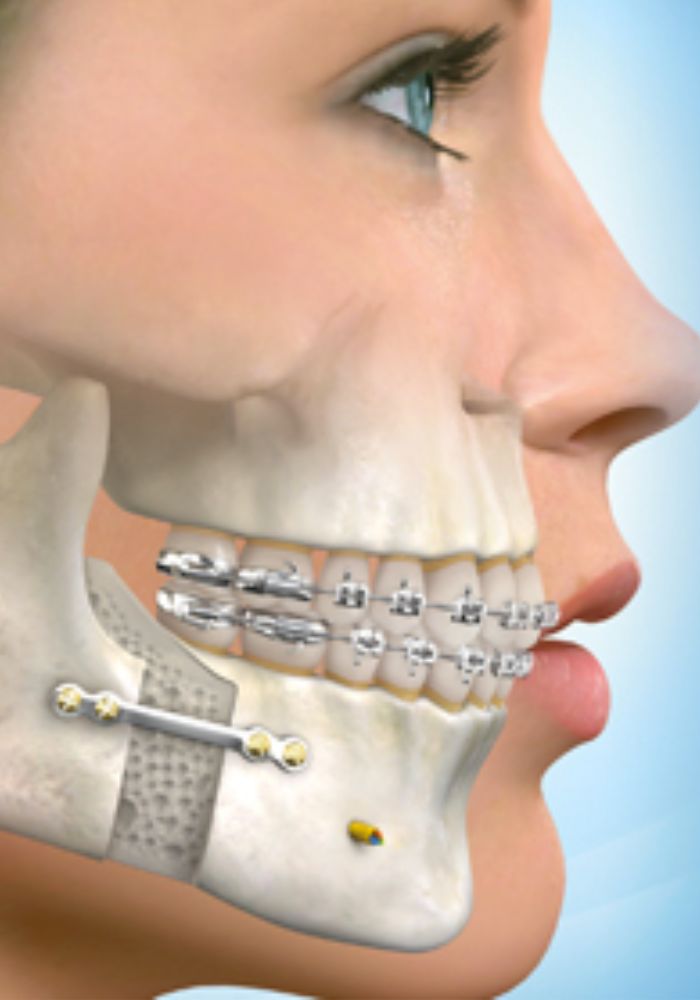

- Planification précise : Une évaluation détaillée et une planification minutieuse sont effectuées en collaboration avec des chirurgiens maxillo-faciaux.

- Suivi orthodontique : Après la chirurgie, des ajustements orthodontiques sont souvent nécessaires pour affiner le résultat.

- Ostéotomie mandibulaire : Réalignement de la mâchoire inférieure.

- Ostéotomie maxillaire : Réalignement de la mâchoire supérieure.

Chirurgie de réduction ou augmentation osseuse

- Correction des anomalies de la forme et de la taille des mâchoires.